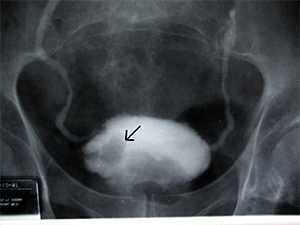

Зондирование сердца заключается в проведении специального катетера в правые или левые отделы сердца. Зондирование позволяет определить кровяное давление в камерах сердца, взять пробы крови на исследование, а также получить изображения желудочков (вентрикулография) и коронарных артерий (коронароартериография) путем введения в них контрастного вещества. При зондировании левых отделов сердца катетер проводят через плечевую или бедренную артерию путем пункции или небольшого разреза. Под контролем рентгеновского экрана катетер вводят ретроградно в аорту и далее в левый желудочек или устья коронарных артерий. После установления катетера в нужном месте вводят контрастное вещество и осуществляют съемку (киноангиография).

Катетеризация левых отделов сердца позволяет определить проходимость коронарных артерий, функцию митрального и аортального клапанов, а также функцию левого желудочка. С ее помощью можно выявить увеличение полости левого желудочка, аортальный стеноз и аортальную недостаточность, расширение корня аорты, митральную недостаточность, аневризму левого желудочка и аорты и патологический сброс крови.

- После установления катетера в нужном месте вводят контрастное вещество для визуализации структур сердца и коронарных артерий.

Нарушение движения стенки сердца свидетельствует о нарушении функции миокарда, обусловленном ИБС, аневризмой, кардиомиопатией или врожденными пороками. Сравнивая размеры левого желудочка в систолу и диастолу, можно судить об эффективности сокращений сердца, фракции выброса, сокращении сегментов стенки. При фракции выброса менее 35% вероятность успешный результатов операции низкая, а риск осложнений после операции высокий. Для поражения клапанов сердца характерен градиент давления на клапане. Так, определение систолического давления над стенозированным аортальным клапаном и под ним обнаруживает градиент давления на клапане. Чем больше градиент, тем более выражен стеноз. Если систолическое давление в левом желудочке равно 200 мм рт. ст., а в аорте - 120 мм рт.ст., то градиент давления на клапане составляет 80 мм рт. ст. В связи с тем что в норме эти показатели давления при открытом аортальном клапане равны, наличие градиента указывает на необходимость хирургической коррекции. Недостаточность митрального клапана проявляется во время вентрикулографии в виде ретроградного заброса контрастного вещества. Дефект перегородки сердца (как межпредсердной, так и межжелудочковой) можно подтвердить, определив содержание кислорода в крови по обе стороны перегородки. Повышение уровня кислорода в крови правых отделов сердца свидетельствует о сбросе крови слева направо, т.е. о дефекте межпредсердной или межжелудочковой перегородки. Снижение уровня кислорода в крови левых отделов сердца указывает на сброс крови справа налево. Сердечный выброс можно определить по уровню кислорода в камерах сердца либо вводя внутривенно контрастное вещество и определяя его концентрацию в момент прохождения мимо термодилюционного катетера.